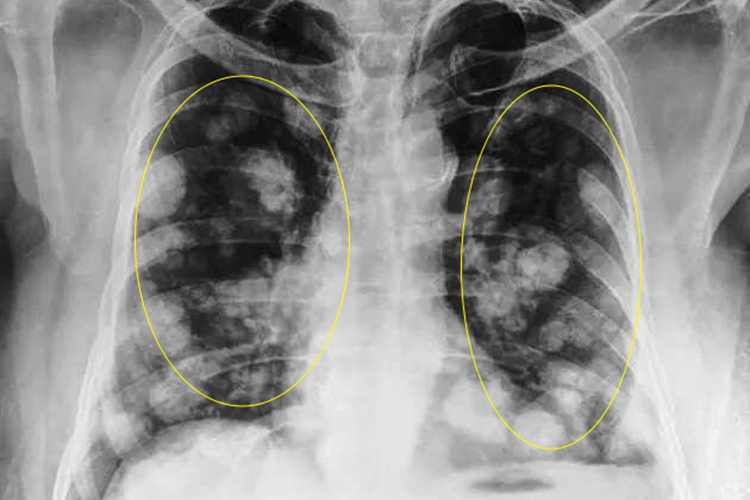

双肺下叶结节灶是指在双侧肺部下叶部位发现的结节样病灶。肺部结节灶是影像学检查(如胸部X线、CT等)中的一种表现。

- 对于双肺下叶结节灶,需要结合结节的大小、形态、密度、边缘特征以及患者的临床症状、病史等多方面因素来综合判断其性质。如果结节较小(一般<8mm),边界清晰、形态规则、密度均匀,多为良性结节,可能是由于既往肺部感染痊愈后留下的瘢痕组织,或者是肺部的淋巴结、良性肿瘤(如错构瘤、硬化性血管瘤等)。

- 如果结节较大(>8mm),形态不规则、边缘有分叶、毛刺,内部密度不均匀,或者伴有空泡征、血管集束征等表现,则恶性结节的可能性就会增加,可能是原发性肺癌,也可能是其他部位的恶性肿瘤转移到肺部所致。